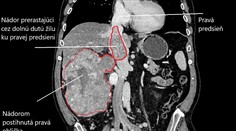

USA Mužovi nevedeli pol roka pomôcť: Napokon mu vyoperovali nádor veľký ako lopta Róbert Ďurkáč 15. 11. 2019